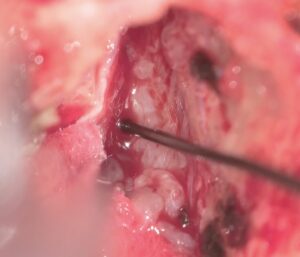

両側のGyrus rectusを剥離、前頭底にいたり、視神経と下垂体茎が見えます。

Trans-lamina terminalis approach、何度もやった古典的なアプローチです。A2と伴奏し縦走する視床下部動脈を温存して、その間隙から腫瘍を減圧していきます。